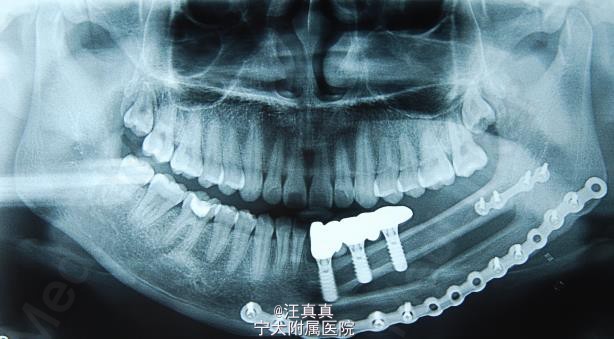

腓骨移植术后的种植修复--下颌骨双折

女,23岁,因肿瘤切除下颌骨体部,行血管化腓骨移植,一年后行种植修复。